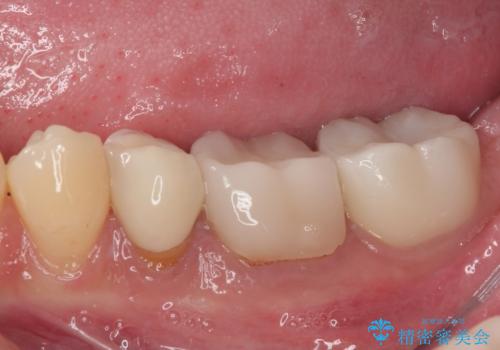

左下奥歯は詰め物と周辺の歯が欠けて、しみている状態でした。

部分的な詰め物ですと、再度破損リスクが高いため、高強度のセラミッククラウンにて補綴治療を行うこととしました。

また、親知らずが埋もれており、よい機会なので抜歯を行ってからセラミッククラウンを装着することとしました。